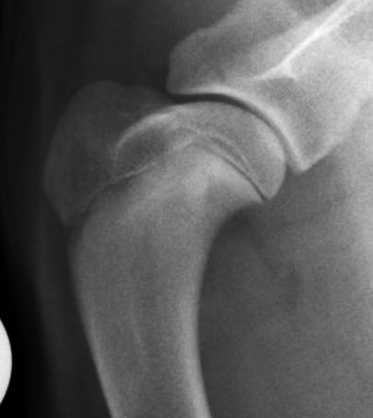

개홍역의 골격계 후유증

보통 후유증으로 틱장애를 가진 신경증상, 치아 애나멜층의 결손등이 거론되는데 방사선상에서 metaphysis의 sclerosis가 유발되는 사례에 대한 보고이다.

참고하고 성견에서 방사선상 이런 병변이 관찰된다면 어린시절 홍역에 감염되었을 가능성이 있는것으로 보고 신경계나 심혈관계 이상에 대한 진단 접근을 해야 할것으로 보인다.